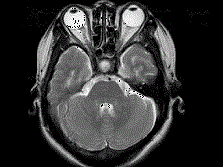

问题 女,41岁,阵发性头痛伴恶心、呕吐20余天.CT影像如图,最可能的诊断为 ( )

选项 A、双侧筛窦息真菌感染 B、双侧筛窦过敏性炎症 C、双侧筛窦炎 D、双侧筛窦未见明显异常 E、双侧筛窦息肉

答案 C